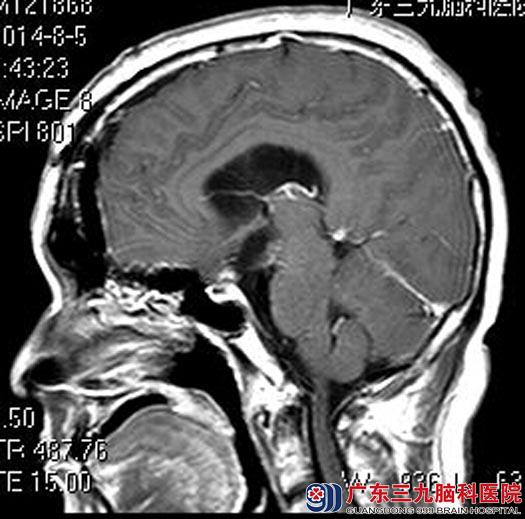

综合神经外科鲁明主任主刀在全麻下行冠状前纵裂终板入路鞍区颅咽管瘤切除术,术中保护神经血管,可见视交叉后囊实性病变,呈灰白色,有完整包膜,血供一般,切开包膜,见草黄色液体,实性肿瘤为白色结晶状,质硬。肿瘤上部与下丘脑、三脑室底粘连,给予钝性分离,肿瘤下部与垂体柄粘连较重,予分离后全切肿瘤,视交叉、双侧大脑前动脉、垂体柄保护完整,经过顺利。术后,陈先生曾出现过一过性离子紊乱,无尿崩症状。现已康复出院。术后病理结果:颅咽管瘤。

手术后